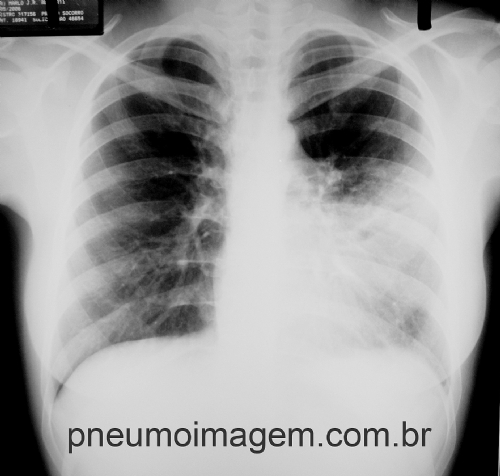

Várias metanálises mostraram que a antibioticoterapia de curta duração (5 a 7 dias) é tão eficaz quanto a terapia de longa duração para pacientes com pneumonia adquirida na comunidade (PAC). Apesar desses achados, a PAC é um dos diagnósticos mais comuns associados ao uso excessivo de antibióticos.

Em um estudo de coorte que avaliou 6481 pacientes hospitalizados com pneumonia nos Estados Unidos de 2017 a 2018, 67% dos pacientes receberam antibióticos por um período excessivo. Entre os pacientes com PAC, a duração média média do antibiótico foi de 8 dias e a duração média do excesso foi de 2 dias.